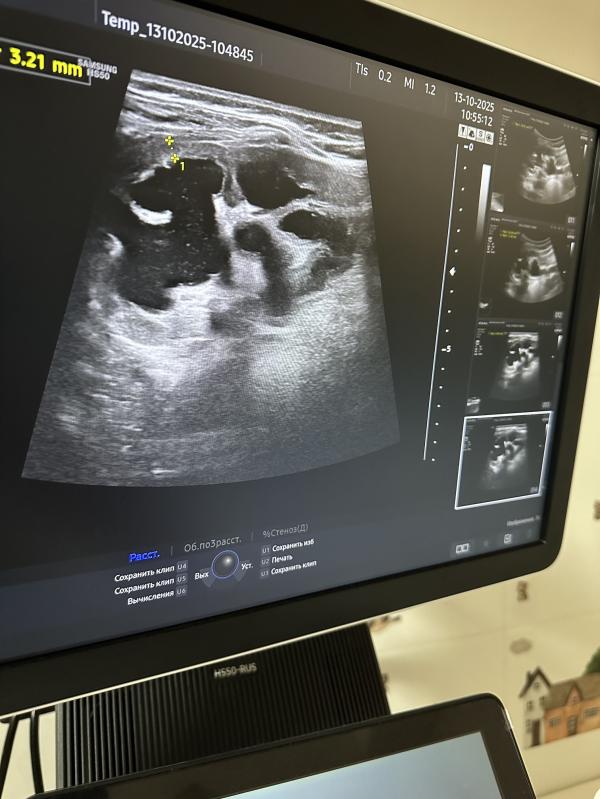

Последующее дополнительное исследование позволило детально рассмотреть левую почку, где обнаружились существенные отклонения: выраженное расширение лоханки, чашечек и мочеточника, а также истончение почечной паренхимы. Подобные изменения свидетельствуют о длительно протекающем патологическом процессе, приводящем к нарушению функций органа.

Позднее, осенью, повторное обследование подтвердило ухудшение состояния: возникло двустороннее расширение чашечно-лоханочной системы (ЧЛС) почек, при этом поражение левой почки приобрело более выраженный характер. Ранее девочка проходила лечение в лечебном учреждении Грозного, где её родителей уведомили о наличии серьёзных проблем и настоятельно рекомендовали обратиться за специализированной медицинской помощью. Впоследствии семья решила проконсультироваться в Северо-Осетинской клинике, однако уровень квалификации специалистов оказался недостаточен, вследствие чего степень угрозы здоровью девочки была недооценена (это моё субъективное оценочное мнение)